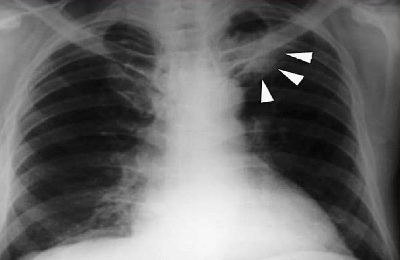

О злокачественном образовании можно говорить, если на рентгене присутствуют следующие признаки:

- Сосуды отклоняются, из-за чего присутствует их дистальное сближение.

- Интенсивность затемнения снижена из-за того, что закупоренный бронх страдает от недостатка вентиляции.

- Наблюдается ателектаз участка легкого (процесс спадения).

Рак экзобронхиального типа проявляется на рентгене такими отличительными чертами:

- наличие гиповентиляции,

- в прикорневой зоне присутствует бугристое образование,

- пятно обладает лучистыми контурами,

- наблюдается сужение просвета бронха,

- увеличение корневых лимфоузлов.